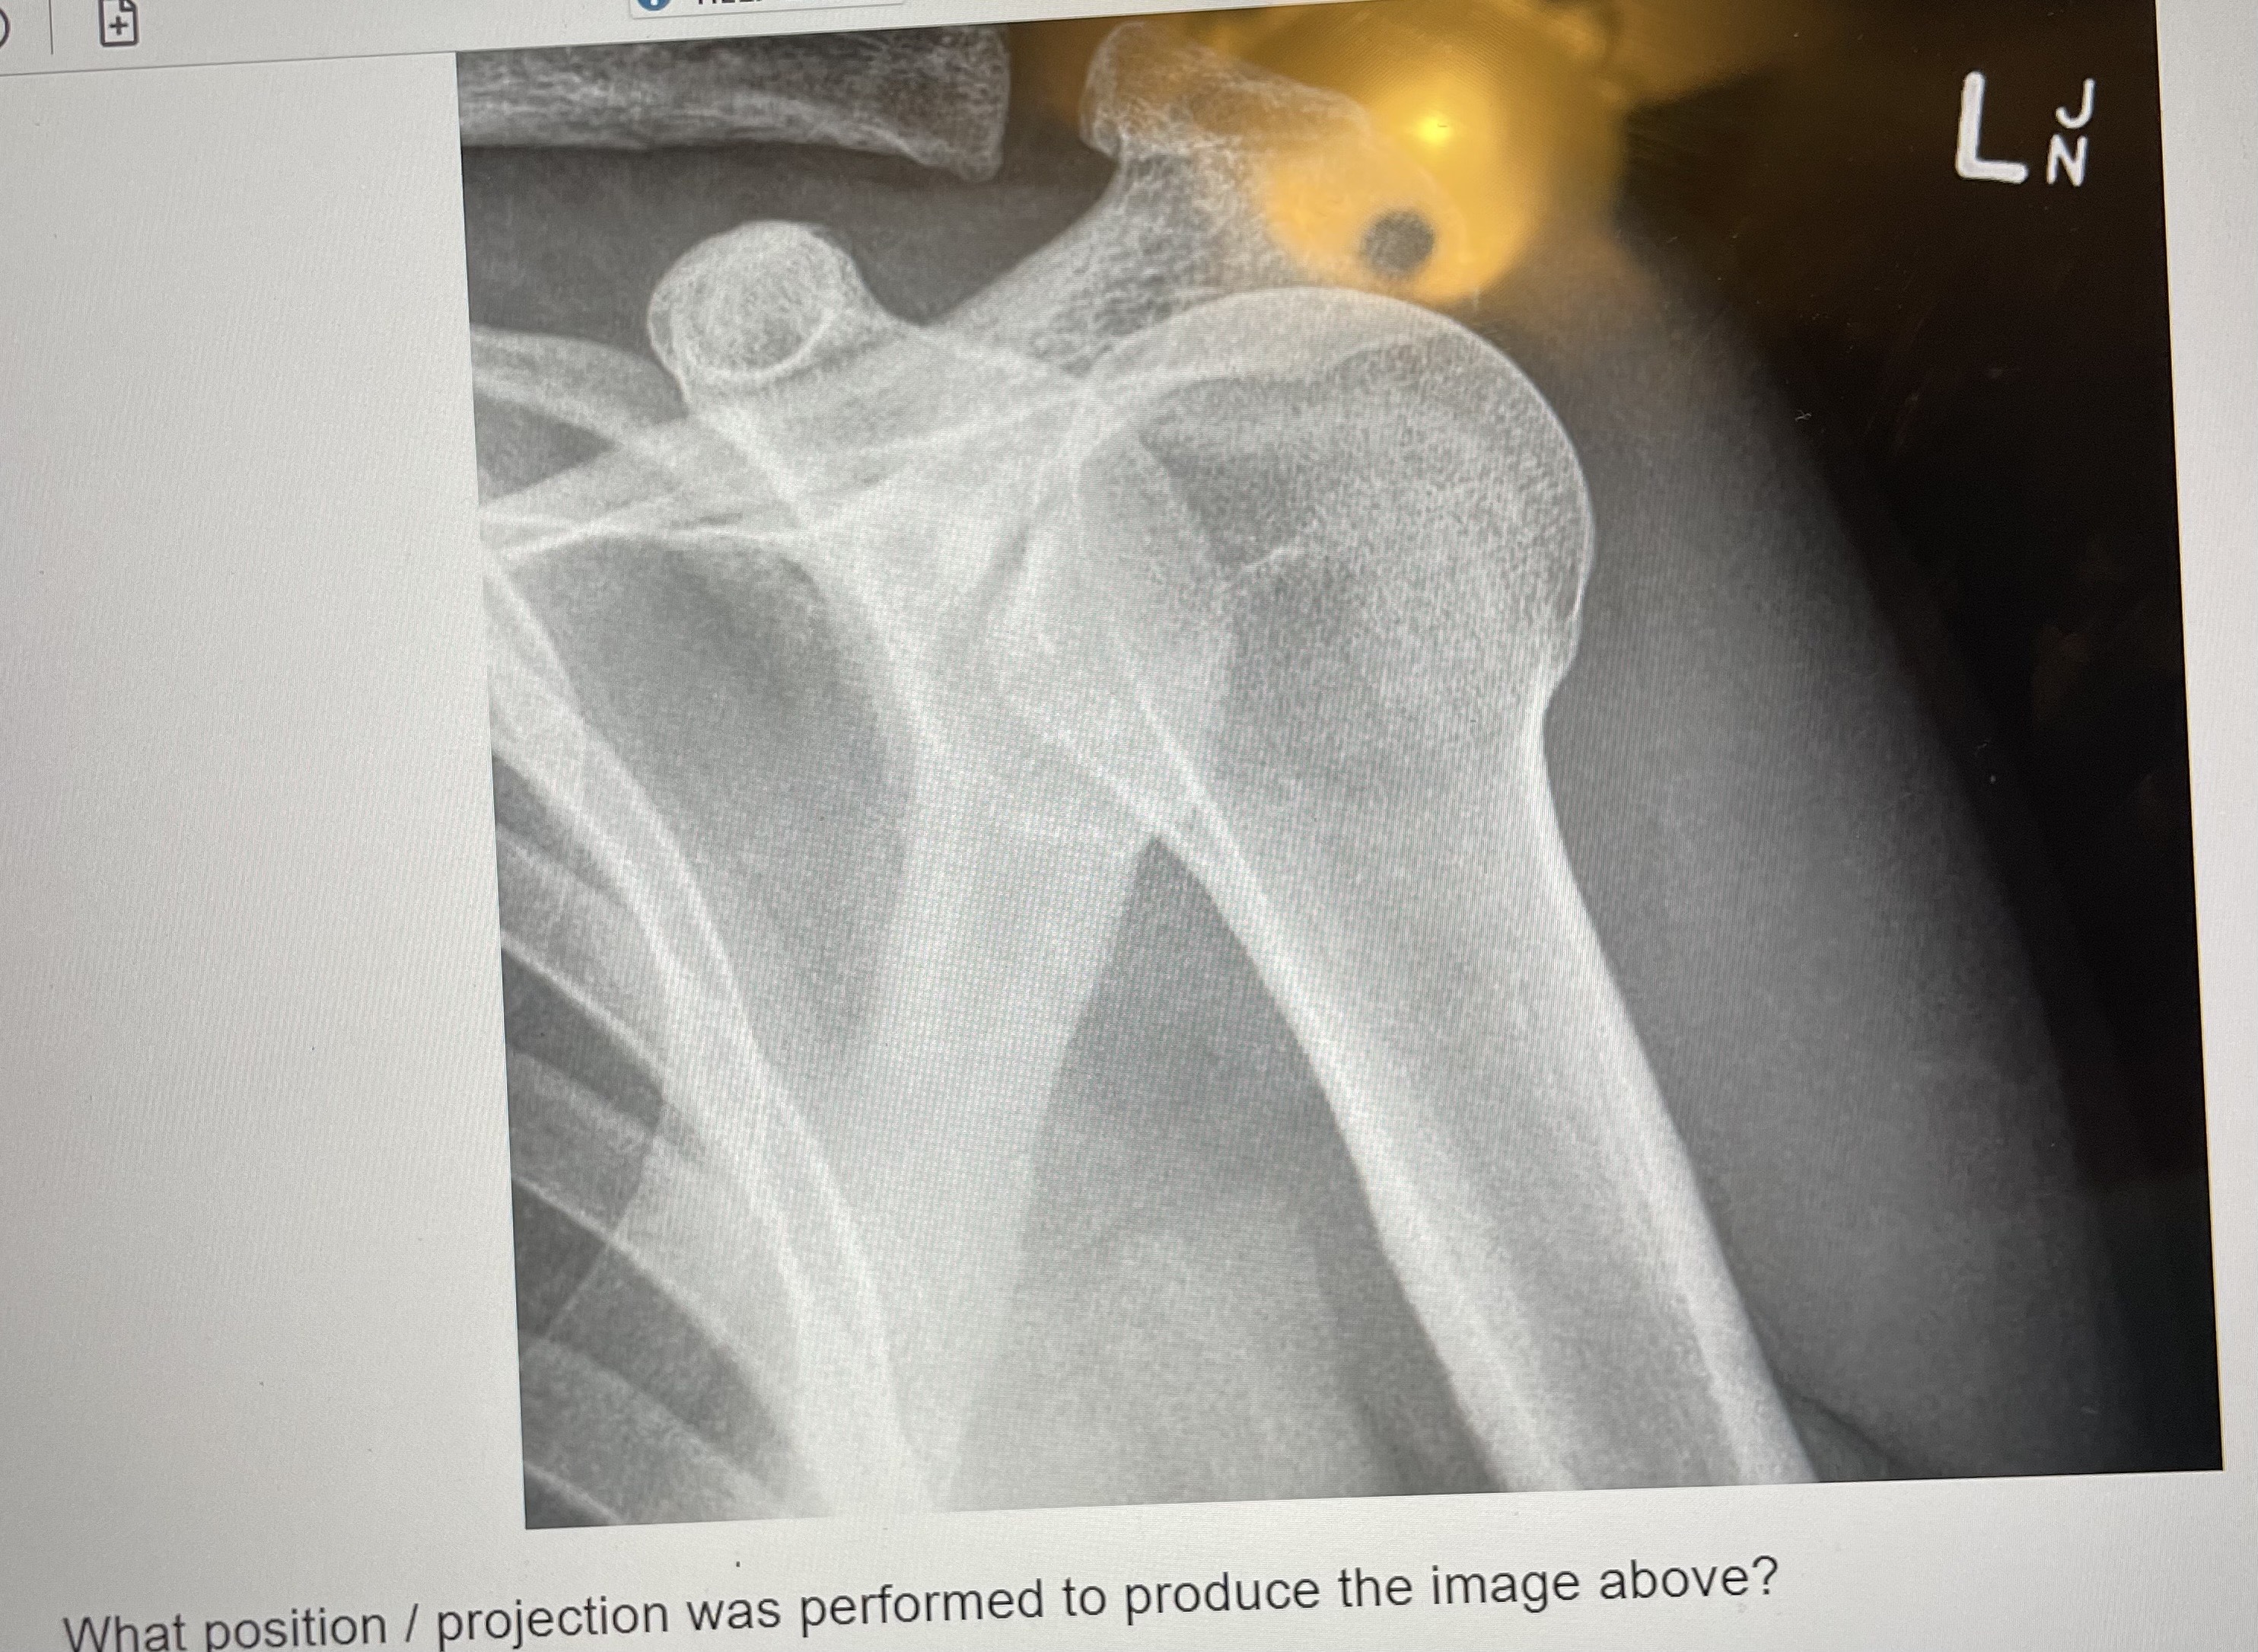

What is the required anatomical structures for an AP of the shoulder?

the entire proximal humerus, the scapula, the majority of the clavicle

The AP projection of the shoulder with the hand supinated will best demonstrate…

greater tuberosity